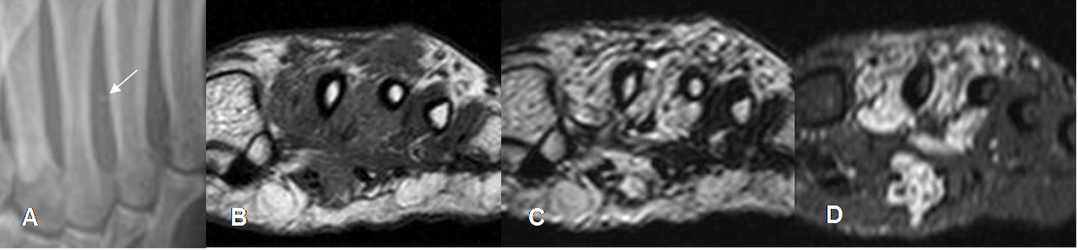

Fig 145. Hemangioma.

A: Rx oblicua. Presencia de flebolito entre el 3º y 4º metatarsianos.

B: RM axial en T1, C: RM axial en T2 y D: RM axial en STIR. Lesión de tejidos blandos que reemplaza la grasa y rodea el 2º, 3º y 4º metatarsianos. Es hipointensa en T1, hiperintensa en T2 y STIR y la presencia de flebolito, sugiere un hemangioma.